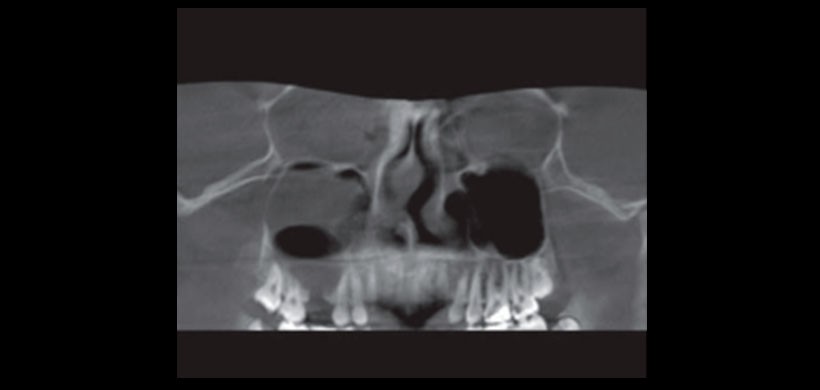

Fig 4. CBCT. A) Antrolito en seno maxilar izquierdo. B) Lesión quística en seno maxilar derecho.